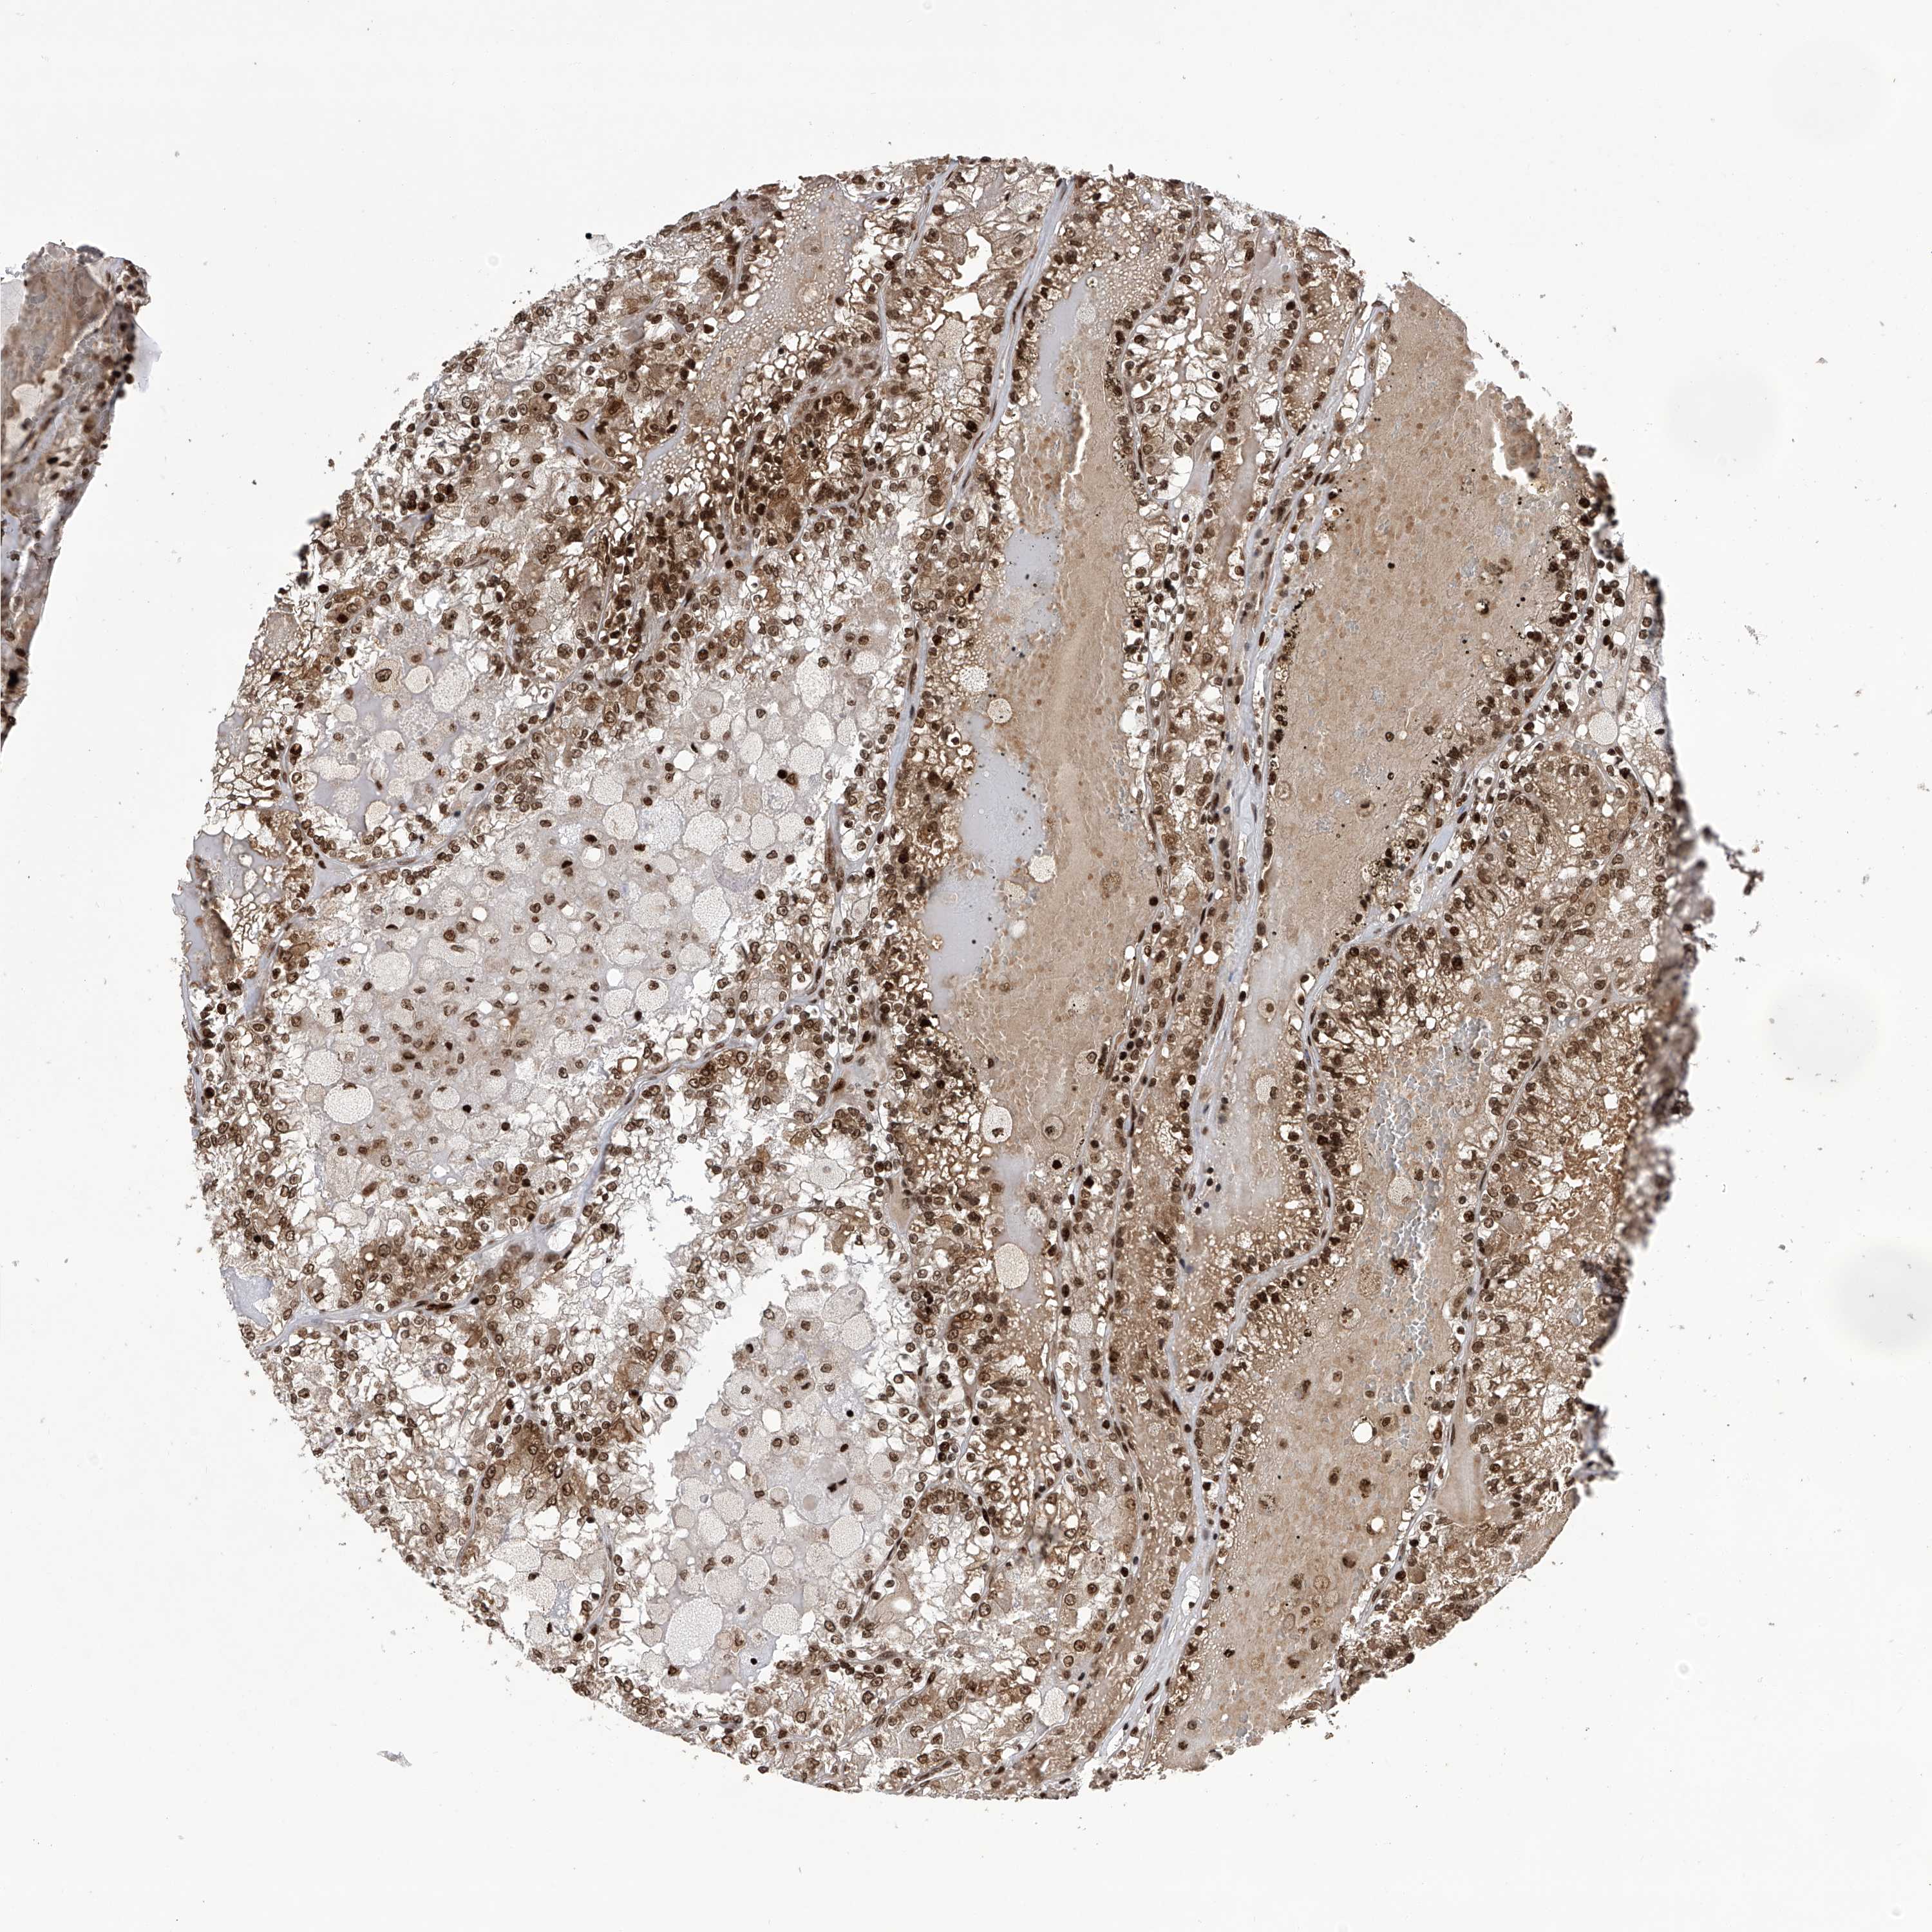

KIDNEY RENAL CLEAR CELL CARCINOMA (VALIDATION) - Interactive survival scatter ploti

The Survival Scatter plot shows the clinical status (i.e. dead or alive) for all individuals in the patient cohort, based on the same data that underlies the corresponding Kaplan-Meier plots. Patients that are alive at last time for follow-up are shown in blue and patients who have died during the study are shown in red.

The x-axis shows the expression levels (FPKM) of the investigated gene in the tumor tissue at the time of diagnosis. The y-axis shows the follow-up time after diagnosis (years). Both axes are complimented with kernel density curves demonstrating the data density over the axes. The top density plot shows the expression levels (FPKM) distribution among dead (red) and alive patients (blue). The right density plot shows the data density of the survived years of dead patients with high and low expression levels respectively, stratified using the cutoff indicated by the vertical dashed line through the Survival Scatter plot. This cutoff is automatically defined based on the FPKM cutoff that minimizes the p-score. The cutoff can be changed by dragging the vertical line or by entering a cutoff value in the square labeled "Current cut-off".

Under the Survival Scatter plot the p-score landscape (black curve; left axis) is shown together with dead median separation (red curve; right axis). Dead median separation is the difference in median mRNA expression between patients who have died with high and low expression, respectively. It is calculated as follows: median FPKM expression of dead patients with high expression - median FPKM expression of dead patients with low expression. This is intended to aid the user in visually exploring custom cutoffs and the associated p-scores and dead median separation.

Individual patient data is displayed and can be filtered by clicking on one or more of the category buttons on the top of the page. Categories describing expression level and patient information include: high, low, alive, dead, female, male and tumor stages. The scale of the x-axis can be toggled between linear and log-scale by clicking on the "x log" button. Mouse-over function shows TCGA ID, patient information and mRNA expression (FPKM) for each patient.

& Survival analysisi

Kaplan-Meier plots summarize results from analysis of correlation between mRNA expression level and patient survival. Patients were divided based on level of expression into one of the two groups "low" (under cut off) or "high" (over cut off). X-axis shows time for survival (years) and y-axis shows the probability of survival, where 1.0 corresponds to 100 percent.

PAK1IP1 is not prognostic in Kidney Renal Clear Cell Carcinoma (validation)

Best expression cut offi

Based on the FPKM value of each gene, patients were classified into two groups and association between prognosis (survival) and gene expression (FPKM) was examined. The best expression cut-off refers the FPKM value that yields maximal difference with regard to survival between the two groups at the lowest log-rank P-value. Best expression cut-off was selected based on survival analysis .

When clicking on this number, the vertical dashed line indicating cut-off, the interactive survival plot, and the Kaplan-Meier curve will be adjusted to show results based on the best expression cut-off.

: 5.69

P scorei

Log-rank P value for Kaplan-Meier plot showing results from analysis of correlation between mRNA expression level and patient survival.

N/A

TCGA RNA samplesi

RNA-seq data is reported as average FPKM (number Fragments Per Kilobase of exon per Million reads), generated by the The Cancer Genome Atlas (TCGA) .

Normal distribution across the dataset is visualized with box plots, shown as median and 25th and 75th percentiles. Points are displayed as outliers if they are above or below 1.5 times the interquartile range. FPKM values of the individual samples are presented next to the box plot.

Average pTPM 8.1

Number of samples 100